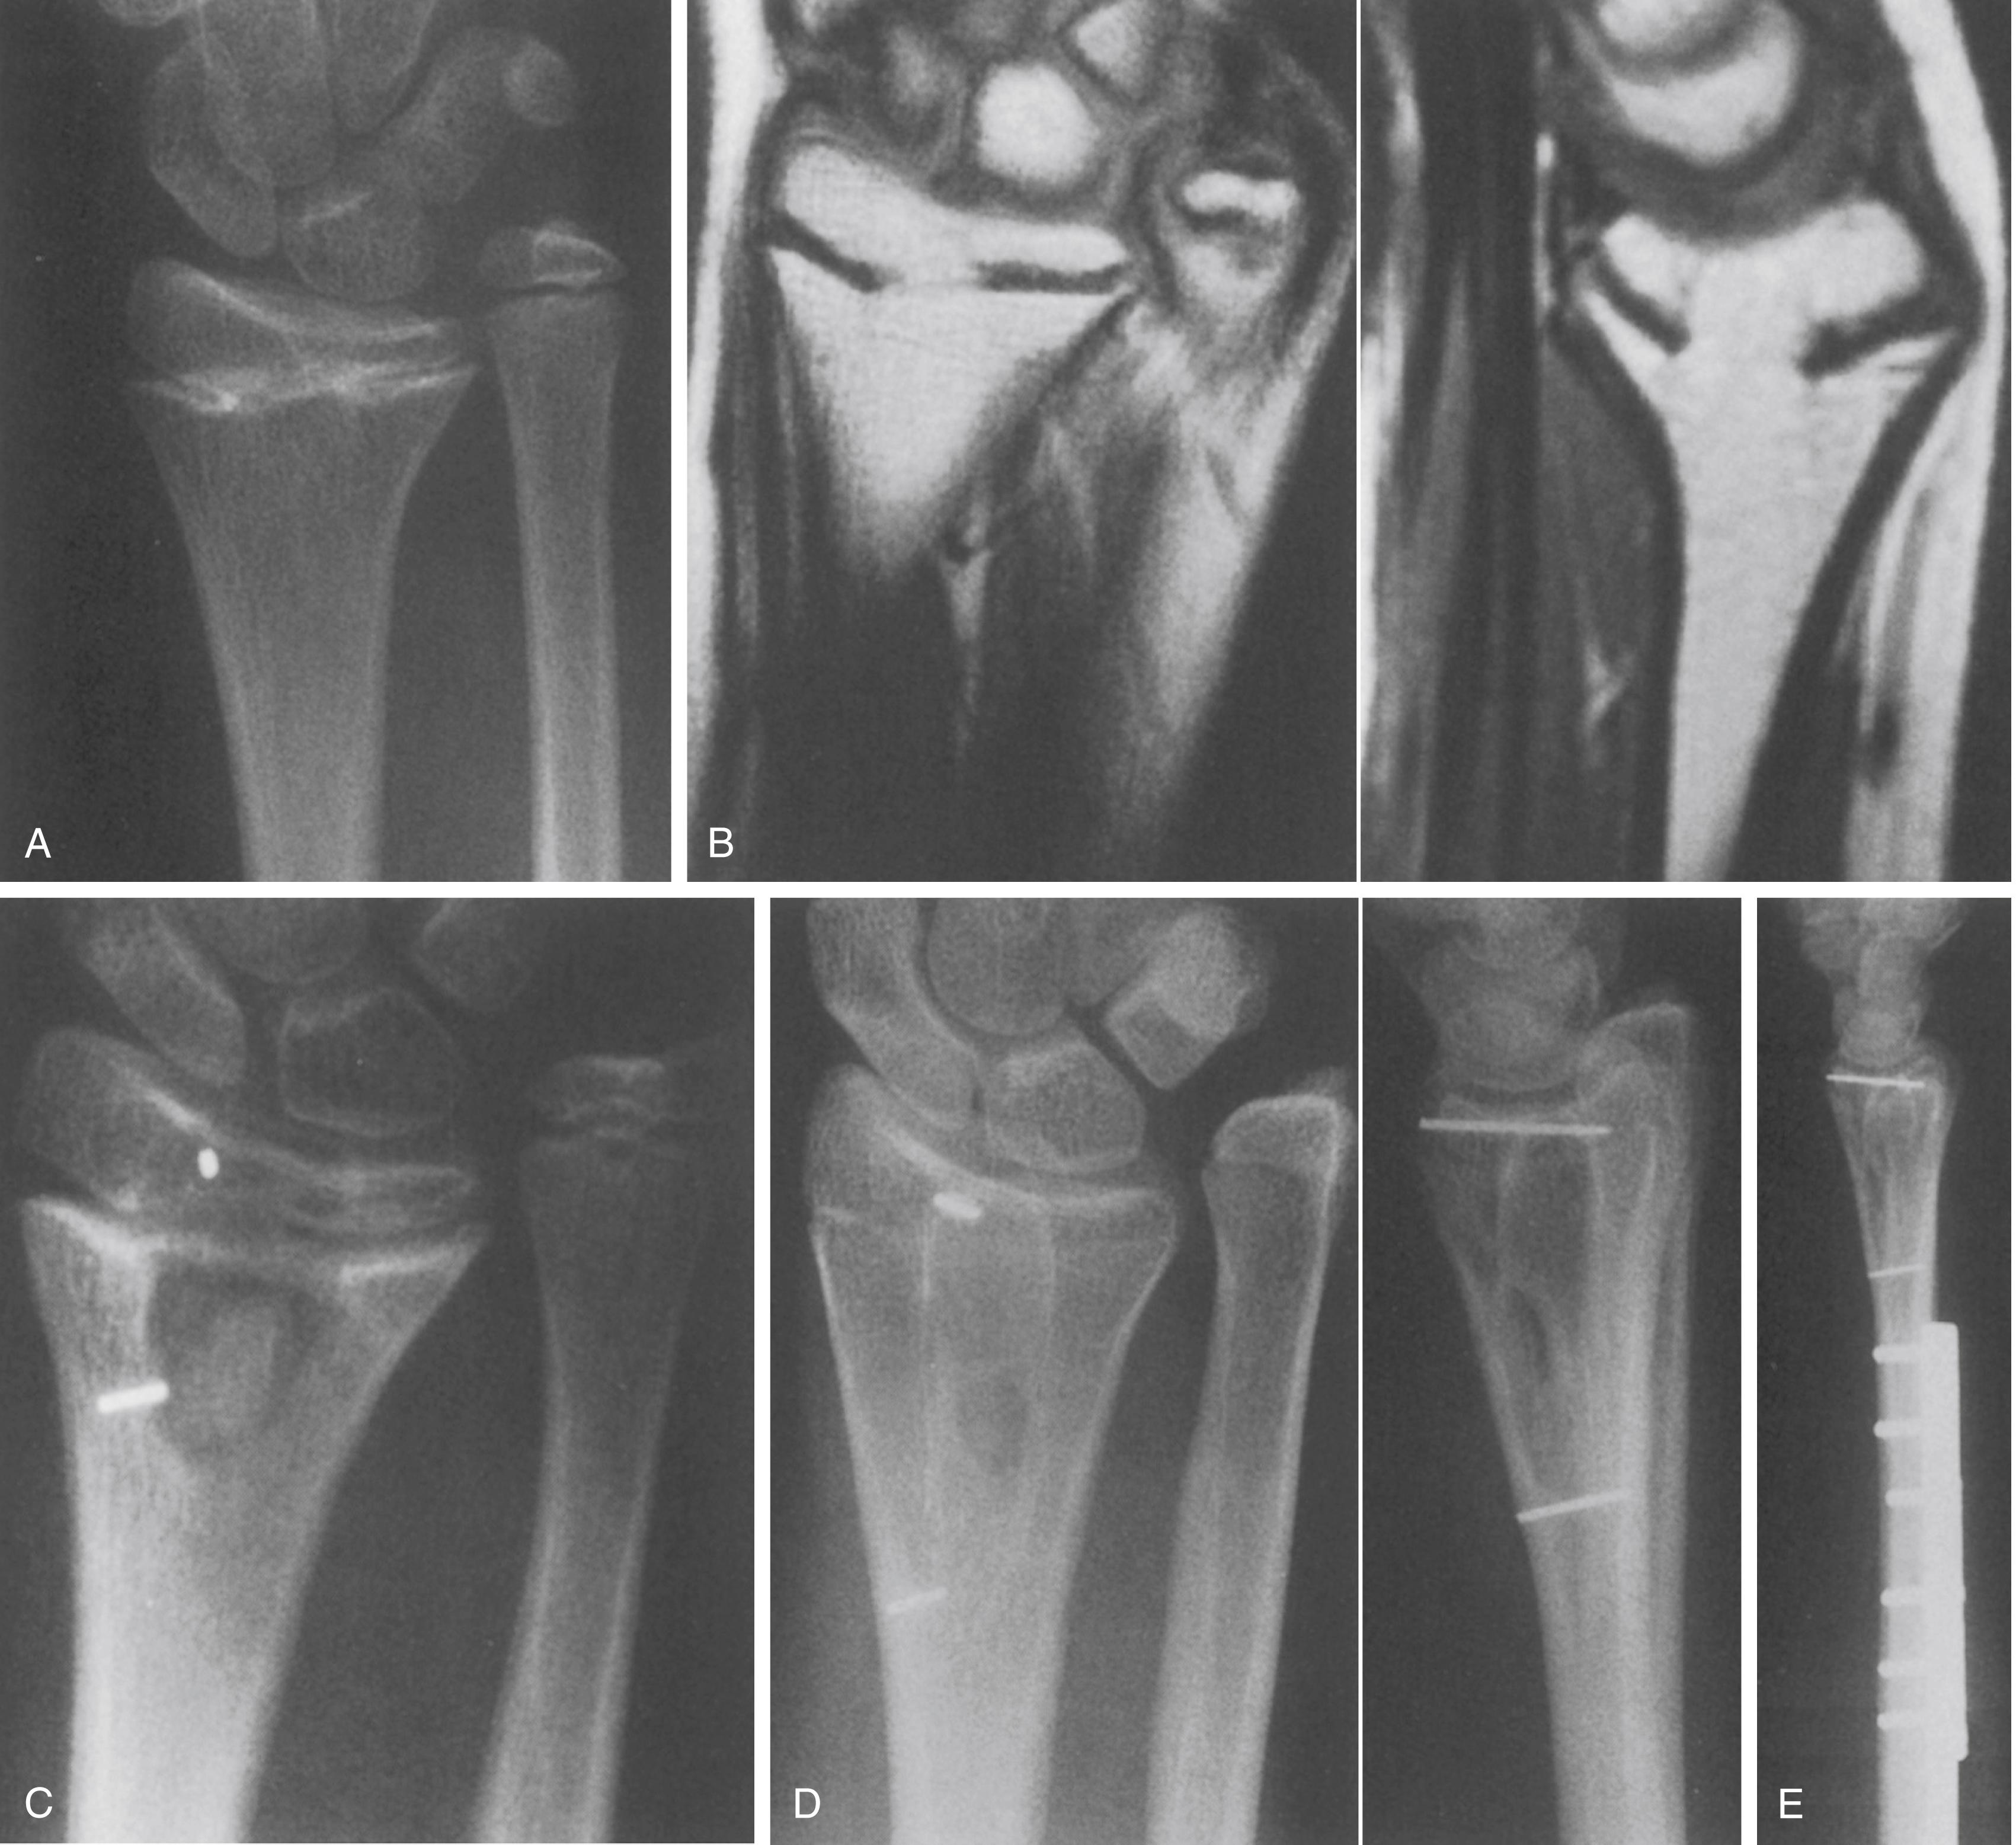

Fig. 27.14, Partial physeal arrest (type b) producing primarily shortening. (A) Anteroposterior (AP) radiograph of the wrist of a 12-year-old girl who had sustained a Salter-Harris type II fracture of the distal radius 6 years earlier. Note the ulnar-positive variance as well as the physeal bar in the center of the distal radius. (B) Coronal and sagittal magnetic resonance images show the extent of the bar. (C) The bar has been resected and metallic markers placed in the epiphysis and metaphysis. (D) AP and lateral radiographs showing resumption of growth, as evidenced by an increased distance between metallic markers. The ulnar-positive variance persists. (E) Lateral radiograph after ulnar shortening to treat symptomatic ulnar-positive variance.